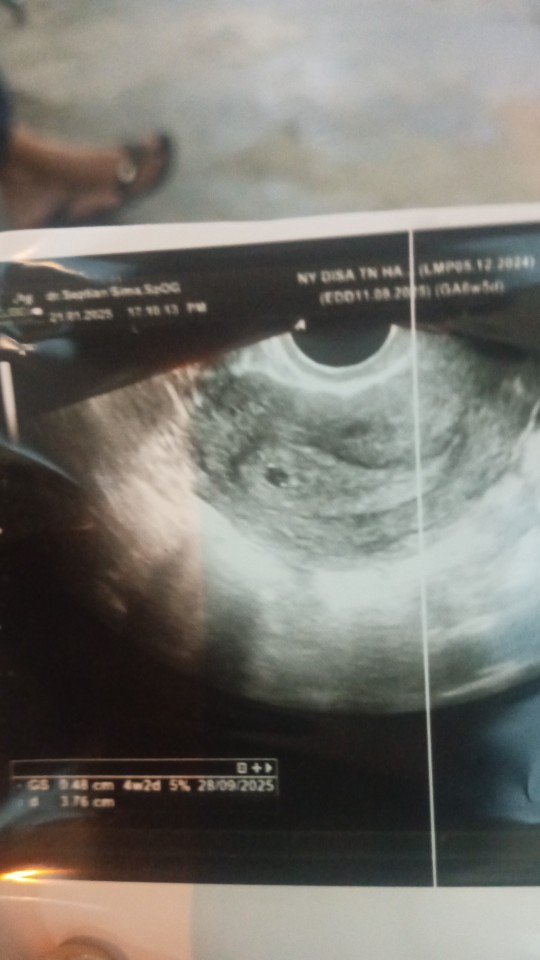

Apakah normal kandungan sudah 6 minggu tapi pas di usg dari segi ukuran masih 4 minggu?

6 minggu menurut hasil usg atau dari hitungan hpht-nya mam?

kantong kehamilannya bund yg kecil skli, katanya ciri² ndg berkembang, sampai dokternya bahas kuret, jdi kefikiran🥲🥲🥲